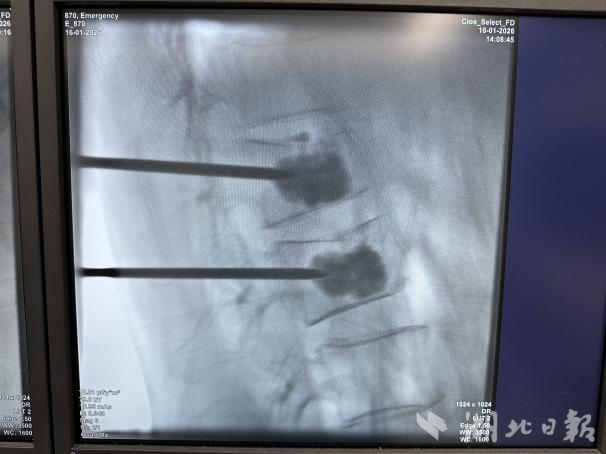

“老师当年教我的时候一丝不苟、严谨求实,如今面对他的病情,我更不敢有丝毫大意。”卢斌医生说。当日中午,手术如期进行。在局部麻醉下,卢斌通过两个不足5 毫米的微小切口,精准向骨折椎体内注入骨水泥,全程仅耗时40 分钟。

术后,卢爷爷的腰痛症状得到明显缓解,复查腰椎CT 显示骨水泥位置十分理想。在卢斌详细交代居家康复要点和抗骨质疏松治疗方案后,当天傍晚,卢爷爷便顺利办理出院手续。从入院到出院,全程不到8 小时,这场“徒弟用所学解师傅燃眉之急”的手术,画上了圆满的句号。

“骨质疏松性胸腰椎骨折是老年人群的常见病,60 岁以上男性同样高发。”陈海丹介绍,轻微外力如跌倒、碰撞甚至剧烈咳嗽,都可能引发椎体压缩骨折,进而造成剧烈疼痛、活动受限,还会因长期卧床诱发致命并发症。而经皮椎板成形术(PVP),正是应对这类骨折的“利器”。该手术通过透视引导精准穿刺,能快速稳定骨折、恢复椎体高度,疼痛缓解率达90%以上。